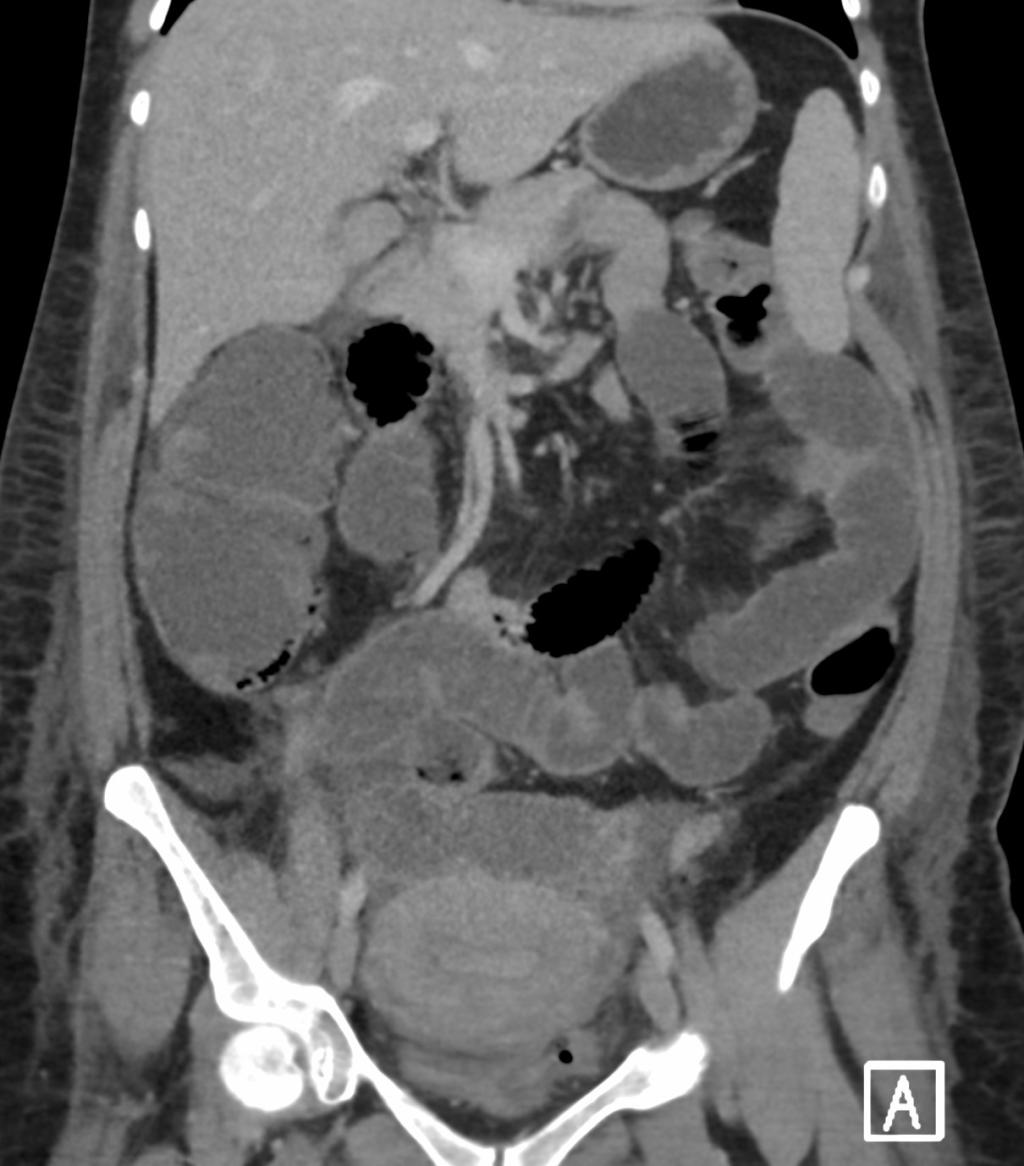

Een CT-scan van het abdomen.

Een 32-jarige, gezonde vrouw wordt 2 dagen na een gecompliceerde sectio caesarea door de chirurg gezien vanwege diffuse buikpijn en braken. Patiënte is ziek en er is sprake van diffuse peritoneale prikkeling. Een CT-scan van het abdomen laat een afwijking van het caecum zien.